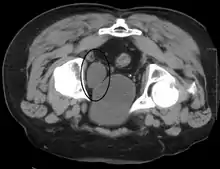

Cross-section of the bladder showing a cancer within it. When a cancer occurs it is most likely to be a transitional cell carcinoma.

Cancer of the bladder is known as bladder cancer. It is usually due to cancer of the urothelium, the cells that line the surface of the bladder. Bladder cancer is more common after the age of 40, and more common in men than women;[28] other risk factors include smoking and exposure to dyes such as aromatic amines and aldehydes.[28] When cancer is present, the most common symptom in an affected person is blood in the urine; a physical medical examination may be otherwise normal, except in late disease.[28] Bladder cancer is most often due to cancer of the cells lining the ureter, called transitional cell carcinoma, although it can more rarely occur as a squamous cell carcinoma if the type of cells lining the urethra have changed due to chronic inflammation, such as due to stones or schistosomiasis.[28]

Investigations performed usually include collecting a sample of urine for an inspection for malignant cells under a microscope, called cytology, as well as medical imaging by a CT urogram or ultrasound.[28] If a concerning lesion is seen, a flexible camera may be inserted into the bladder, called cystoscopy, in order to view the lesion and take a biopsy, and a CT scan will be performed of other body parts (a CT scan of the chest, abdomen and pelvis) to look for additional metastatic lesions.[28]

Treatment depends on the cancer's stage. Cancer present only in the bladder may be removed surgically via cystoscopy; an injection of the chemotherapeutic mitomycin C may be performed at the same time.[28] Cancers that are high grade may be treated with an injection of the BCG vaccine into the bladder wall, and may require surgical removal if it does not resolve.[28] Cancer that is invading through the bladder wall may be managed by complete surgical removal of the bladder (radical cystectomy), with the ureters diverted into a segment of part of ileum connected to a stoma bag on the skin.[28] Prognosis can vary markedly depending on the cancer's stage and grade, with a better prognosis associated with tumours found only in the bladder, that are low grade, that don't invade through the bladder wall, and that is papillary in visual appearance.[28]